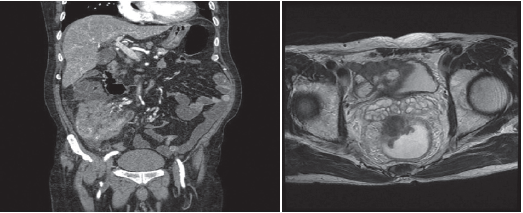

간 질환

간은 인체에서 가장 큰 장기 중 하나로, 여러 가지 중요한 기능을 수행합니다. 간 질환은 매우 일반적인 문제로, 신속하고 정확한 진단이 필요합니다. 복부 CT를 통해 간의 경화, 종양, 지방간 등 다양한 문제를 확인할 수 있습니다. 특히 간암의 경우, CT 촬영은 초기 단계에서 종양의 크기와 위치를 평가하는 데 중요한 역할을 합니다. CT 이미지는 간 내 혈관과 주변 조직의 상태를 상세히 보여주기 때문에, 간암이 다른 장기로 전이되었는지 파악하는 데도 유용합니다.

신장 질환

신장은 인체의 대사 노폐물을 제거하고 수분 및 전해질 균형을 유지하는 중요한 역할을 합니다. 신장에 문제가 발생하면 체내의 여러 기능이 부정적인 영향을 받을 수 있습니다. 복부 CT는 신장 결석, 신장 종양 및 기타 신장 관련 질환을 진단하는 데 도움을 줍니다.